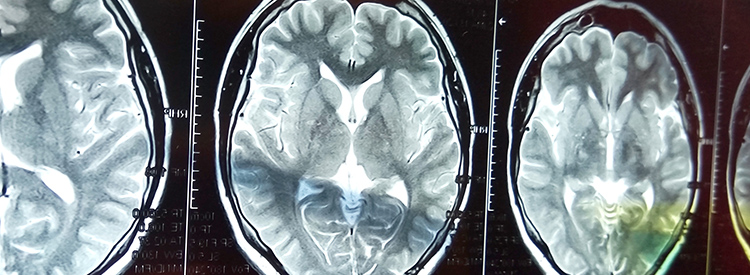

中風治療進展緩慢。如果在最初幾分鐘內(nèi)進行治療,可以在急診室或醫(yī)院使用特殊藥物(阿替普酶或組織纖溶酶原激活劑)來逆轉(zhuǎn)或限制缺血性中風造成的損害。這種藥物可以分解阻塞血管的凝塊。如果在最初的幾分鐘到幾小時內(nèi)使用,可以避免或限制對大腦的任何損害。在使用阿替普酶之前,必須進行 CT 成像來確定中風類型,以確認中風不是出血性的。由于阿替普酶會分解血栓,因此如果用于出血性中風,可能會導致嚴重惡化或死亡。有時會治療出血性中風以避免進一步出血。